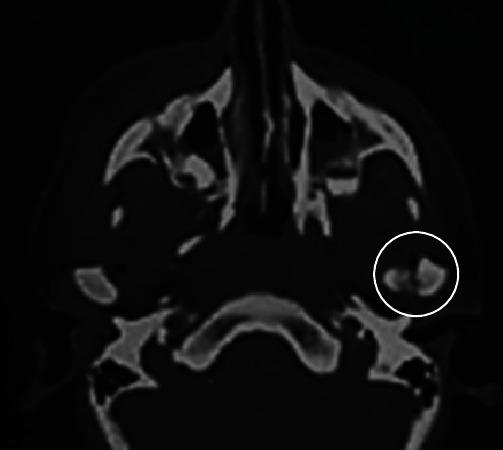

Temporomandibular joint ankylosis is an important entity that dentists and maxillofacial surgeons should know about. It clinically manifests through a permanent limitation of mandibular movements coupled with mouth opening inferior to 3 cm. This serious pathology can have serious functional repercussions, such as mastication problems, speech troubles, eating disorders, and jaw growth hindrance, in addition to the psychological difficulties in coping with such a condition in daily life. Herein, we present a radiological and chronological illustration of the evolution of temporomandibular joint ankylosis following an overlooked traumatic fracture of the mandibular condyle. The present case report involves an 8-year-old patient referred for a gradually evolving mouth opening limitation following a car accident. Tomodensitometry was helpful as it revealed an osseous block between the left temporomandibular joint surfaces, showing an ankylosis. Posttraumatic cerebral computed tomography scan was performed. It revealed an undetected fracture of the left condyle. The aim of this paper was to show how a traumatic ankylosis could have been avoided if enough attention was paid to the interpretation of immediate posttraumatic computed tomography scans. A thorough dental examination must be carried out once vital emergency is over. Early diagnosis of temporomandibular joint trauma is a crucial factor in preventing complications, such as ankylosis and its consequent oral dysfunctions. The dentist must automatically suspect condylar fracture when a child presents a history of head trauma, especially a mandibular trauma. This case should be a reminder that although temporomandibular joints are very often left out in patients' vital emergency first examination, temporomandibular joints/they are still a highly important structure which omission, and thus, dysfunction, if lesions are present, can lead to nonnegligible medico-legal consequences/that temporomandibular joints should be taken into account during patients' vital emergency first examination because if they are neglected, in the presence of lesions, they cause dysfunction, thus leading to nonnegligible medico-legal consequences.

颞下颌关节强直是牙医和颌面外科医生应该了解的一种重要病症。其临床症状表现为下颌运动永久性受限,伴张口度小于3厘米。这种严重的病理状况会产生严重的功能影响,如咀嚼问题、言语障碍、进食紊乱以及颌骨生长受阻,此外还会给日常生活中应对这种状况带来心理困扰。在此,我们展示了一例因下颌髁突创伤性骨折被忽视后颞下颌关节强直演变过程的影像学及时间顺序说明。本病例报告涉及一名8岁患者,因车祸后逐渐出现张口受限前来就诊。计算机断层扫描有助于诊断,因为它显示左侧颞下颌关节面之间存在骨块,提示关节强直。同时进行了创伤后脑计算机断层扫描,结果显示左侧髁突有一处未被发现的骨折。本文旨在表明,如果在创伤后立即进行的计算机断层扫描解读中给予足够重视,创伤性关节强直是可以避免的。一旦度过重要的紧急情况,必须进行全面的牙科检查。颞下颌关节创伤的早期诊断是预防诸如关节强直及其导致的口腔功能障碍等并发症的关键因素。当儿童有头部外伤史,尤其是下颌外伤史时,牙医必须自动怀疑有髁突骨折。这个病例应提醒人们,尽管在患者重要紧急情况的初次检查中颞下颌关节常常被遗漏,但颞下颌关节仍然是一个非常重要的结构,若存在病变而被遗漏,进而导致功能障碍,可能会引发不可忽视的医疗法律后果,即在患者重要紧急情况的初次检查中应考虑颞下颌关节,因为如果忽视它们,在存在病变时会导致功能障碍,从而引发不可忽视的医疗法律后果。